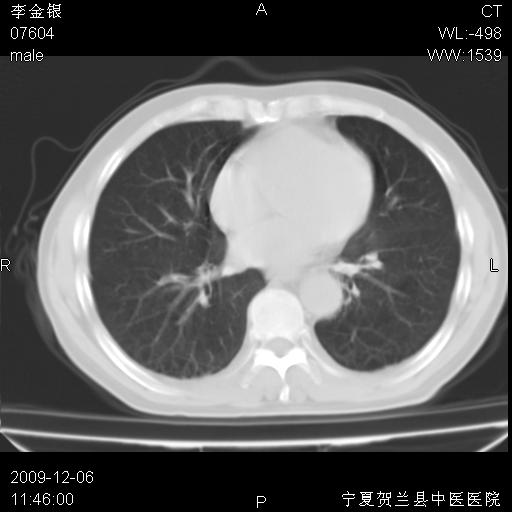

该病人 ,男,62岁,主因咳痰带血两天

考虑右肺中央型占位性病变并阻塞性肺炎.(右肺上叶支气管变窄),建议支纤镜检查.

考虑右肺中心型肺癌伴阻塞性肺炎及右肺门淋巴结转移,建议纤维支气管镜进一步检查。

支气管壁明显增厚 管腔狭窄,腔静脉后多个淋巴肿大,结合年龄病史考虑右肺上叶中央型肺癌并阻塞性肺炎

右肺上叶后段支气管阻塞,右上肺门占位,相应肺段阻塞性肺炎,右肺门有淋巴结肿大。诊断右肺上叶中心型肺癌,阻塞性肺肺炎、右肺门淋巴结转移。

符合中央型肺癌的ct表现并肺出血。但有一点腔静脉后有一钙化的淋巴结啊

右上叶支气管狭窄,管壁增厚,远端斑片状软组织影,病灶邻近叶间裂,叶间裂无移位。

诊断右肺中央型肺癌。

那个片影应该大部分都是病灶,病灶沿肺段支气管分支生长,后段完全显示不清、闭塞。若为不张应该伴有叶裂的移位,若为炎症应有空气支气管征。

右肺中心型肺癌伴阻塞性肺炎及右肺门与纵膈淋巴结转移很典型,可纤维支气管镜进一步检查

考虑右侧中央型肺癌伴右肺上叶后段阻塞性炎症、肺不张、右肺门和纵隔淋巴结肿大。

右肺上叶中心型肺癌,阻塞性肺炎、右肺门和纵隔淋巴结转移。